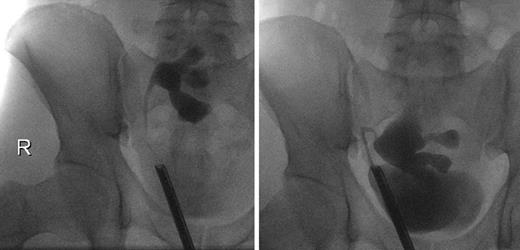

On the 51st postoperative day, the patient presented an elevated creatinine of 241 μmol/L and a stable hydronephrosis, so that a stent insertion was necessary. The retrograde ureteropyelography showed no pathologies (Fig. 2), and the creatinine levels decreased afterwards. The perfusion of the kidney was adequate. The removal of the ureteral stent was successfully performed 3.5 months later. In the 9th postoperative month, a scintigraphy was performed and showed a functional obstruction of the kidney transplant, so that we initially refrained from further interventions.

Ureteropyelogram 6 weeks (left) and 9 months (right) after kidney transplantation.

The following ultrasound controls showed a progredient hydronephrosis, requiring a reinsertion of the ureteral stent. Furthermore, the patient reported a hypermobility of the transplant in his pelvis. The intraoperative ureteropyelography confirmed this by showing a hypermobility of the kidney depending on the degree of bladder filling (Fig. 2). According to this diagnosis, a robot-assisted transplant nephropexy was performed. Further sonographic controls showed a stable pelvic ectasia with stable creatinine levels around 111 μmol/L.